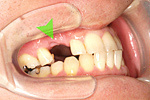

症例 9

① 右上34番の歯がありません。

② インプラントで2本分の歯を作りました。

20才代 男性

総額:45万円(税別)

治療期間:3ヵ月

リスク副作用:骨の吸収による審美性の低下。ブラッシング不良によるインプラント周囲炎の発生。